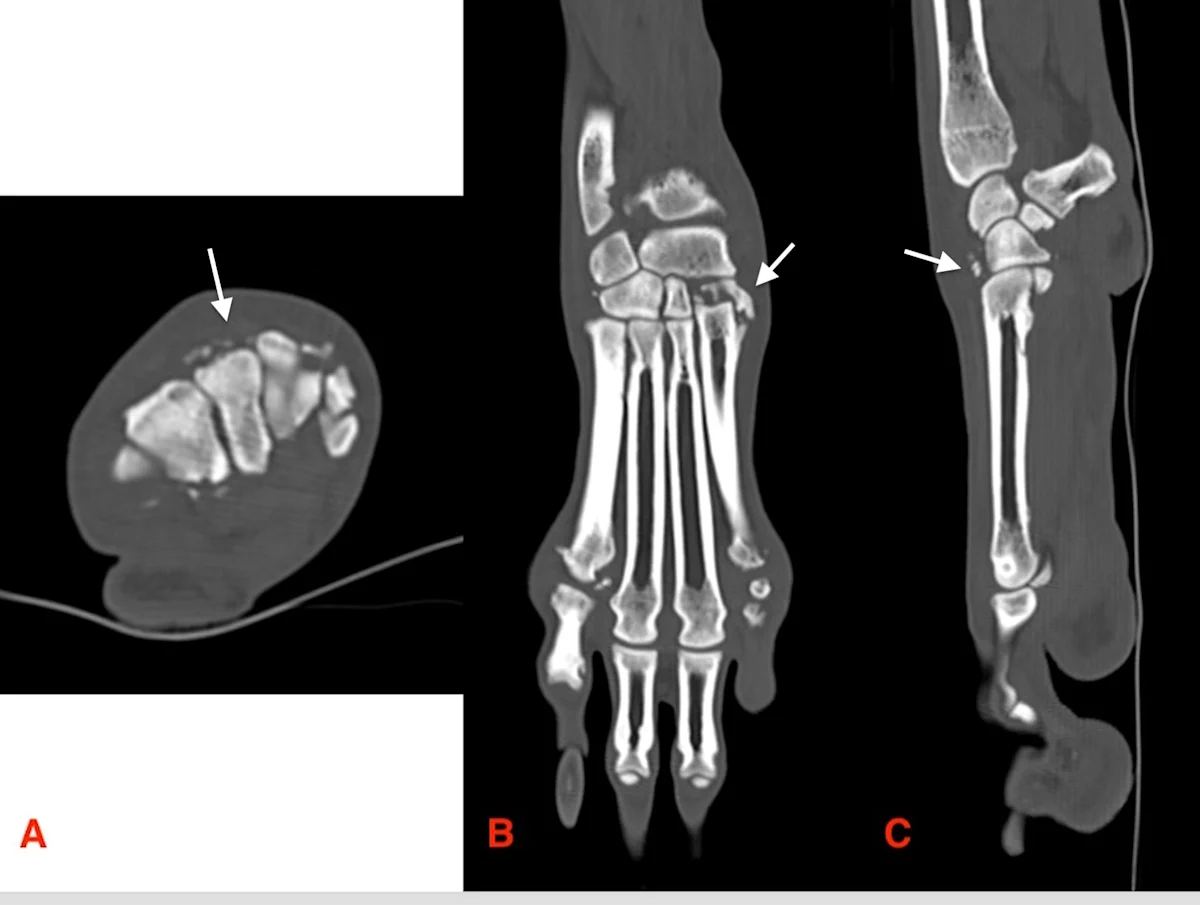

Normal standing angles of the carpus and tarsus are 10 to 12 degrees and 135 to 145 degrees, respectively, in dogs and 12 to 15 degrees and 115 to 125 degrees, respectively, in cats.3,4 Sedation is often required to determine whether there is instability in the medial, lateral, cranial, or caudal directions (Figure 3).

Stress radiography was performed using a radiolucent object (ie, a wooden block) to apply stress on the right tarsus of a dog. Stress must be applied in all directions, including in flexion (A), extension (B), valgus (C), and varus (D).